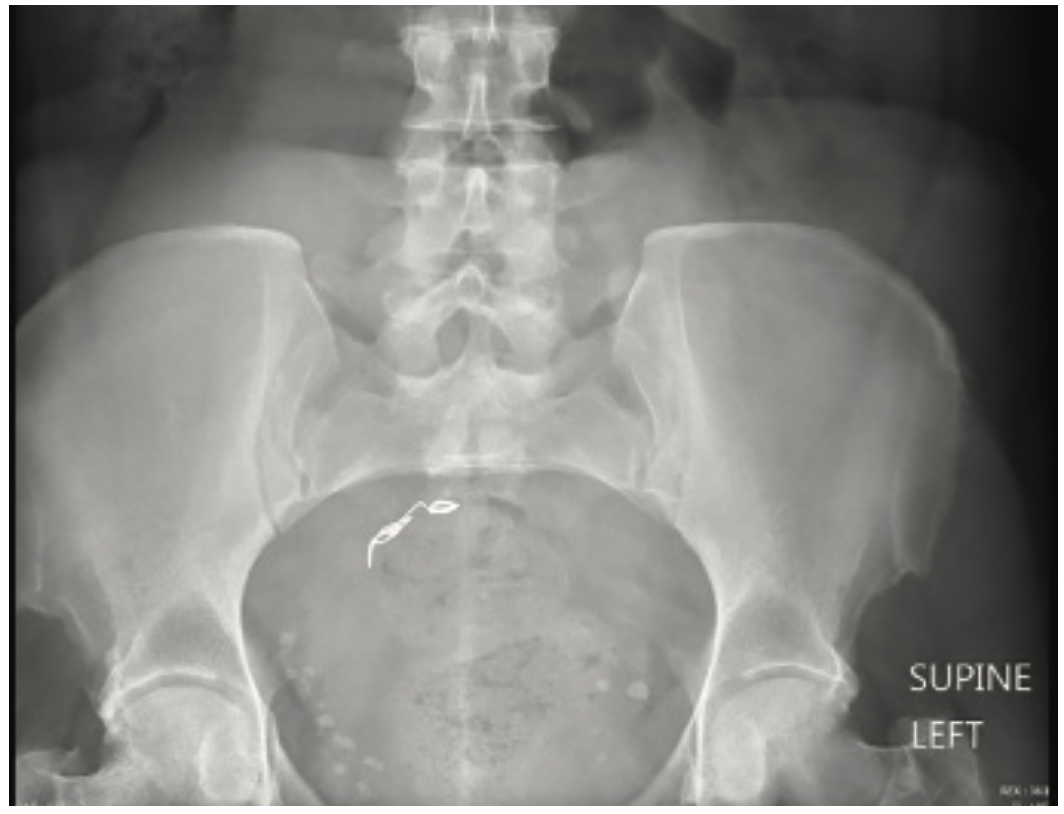

Coil Embolization to the Right Side of the Heart After Elective Coil Embolization Wiki healthcare providers use endovascular coiling to block blood flow into an aneurysm. This procedure is also called. an embolization procedure blocks a specific blood vessel to stop abnormal bleeding. coil embolization is an alternative therapy that involves packing platinum coils into an aneurysm through a microcatheter in an. With the evolution of coil technology, today’s interventional. It. Coil Embolization Wiki.

Coil Embolization to the Right Side of the Heart After Elective Coil Embolization Wiki coil embolization is an alternative therapy that involves packing platinum coils into an aneurysm through a microcatheter in an. It uses substances (embolic agents) that. healthcare providers use endovascular coiling to block blood flow into an aneurysm. an embolization procedure blocks a specific blood vessel to stop abnormal bleeding. With the evolution of coil technology, today’s interventional.. Coil Embolization Wiki.